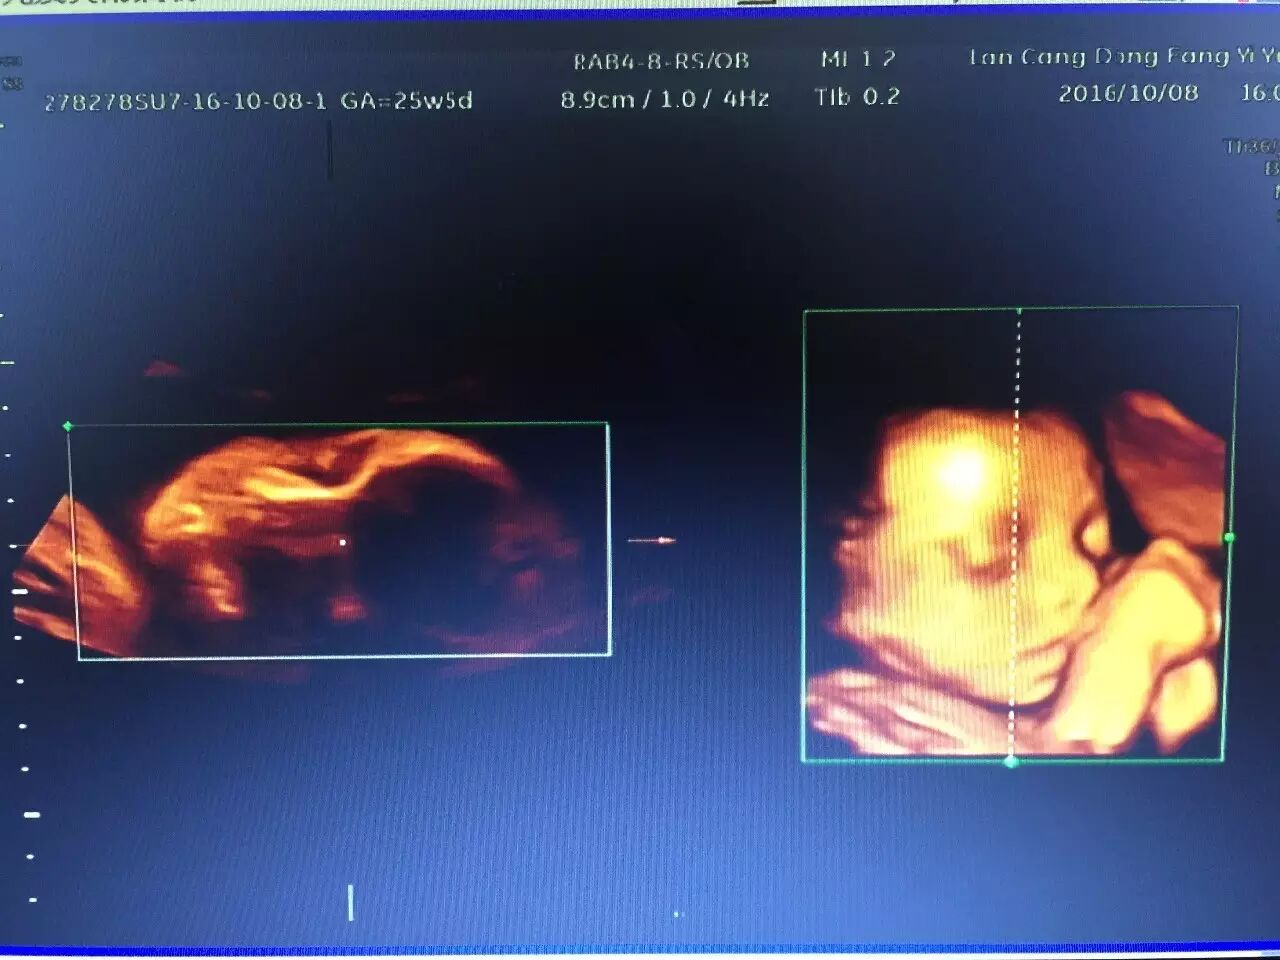

我院引进了美国GE公司的四维彩色超声诊断仪,四维彩超的全称为四维彩色超声诊断仪,是世界上最先进的彩色超声设备。

其结果是:这种高科技设备能够显示你未出生的宝宝的即时动态活动图像,或者人体内脏器官的即时活动图像。

与 3D超声波成像系统相比,四维彩色B超可以使得医生即时地观察胎儿在子宫内的动态运动,判断胎儿的发育情况。

其优点一改既往二维超声中黑白色调的静态平面图像,而变成有色彩的立体动态的人体器官(包括胎儿)的实时活动图像,使医生的诊断更精确、可靠

排查胎儿发育是否畸形,可以清楚的看到孩子的发育情况,除了能看到孩子的五官发育,四肢发育以外,内部心脏,肾脏发育,脊柱发育,脑部发育四维彩超也能清楚的看到。